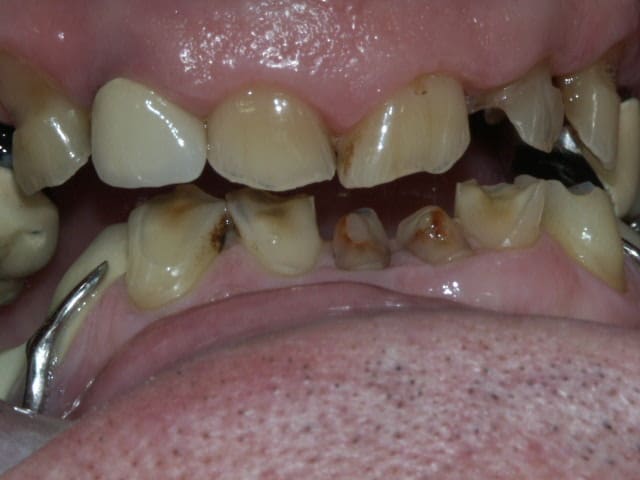

bon, difficile d'évaluer à distance...au vue de la pano et de tes photos...voilà ce que je ferais...:

-extrac de 14 et 27

-après les dévit qui s'imposent (même avec la pulpe dans les chaussettes)bridge sup en 2 parties, de 11 à 16 (que tu peux garder vivante) et 21 à 26

-Bridges inf en 3 parties, 33 à 37, 32 à 42, 43 à 47

tout à fait. C'est un monsieur charmant de 68 ans. Il vient pour voir ce qu'on peut faire, pas le genre à être un chiant, du tout. Il est conscient de son problème et de la difficulté à le traiter.

Le constat est le suivant, corrigez-moi si je me trompe:

on a eu des extractions non compensées à la mandibule qui ont provoquées des égressions des dents maxillaires postérieures.

une abrasion +++ du bloc antérieure avec égression "physiologique" au fur et à mesure de l'usure.

On a ainsi un décalage important (comme une marche d'escalier) de la courbe d'occlusion (Spee) entre le secteur antérieur et postérieur.

La difficulté de la thérapeutique consistera à rattraper le mieux possible ce décalage pour avoir une courbe d'occlusion "harmonieuse".